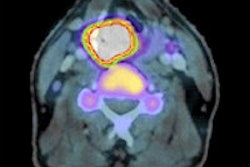

Dutch molecular imaging developer MILabs has launched its mini product family with the release of benchtop SPECT and PET systems for small-animal imaging.

The mini product line has been developed for laboratory researchers who have limited space and/or budgets to provide solutions for high-quality SPECT and/or PET imaging.

Features of the U-SPECT mini, the U-PET mini, and the VECTor mini include high resolution, list-mode acquisitions, fast dynamic modes, high-precision reconstruction algorithms, and multimodality connectivity.